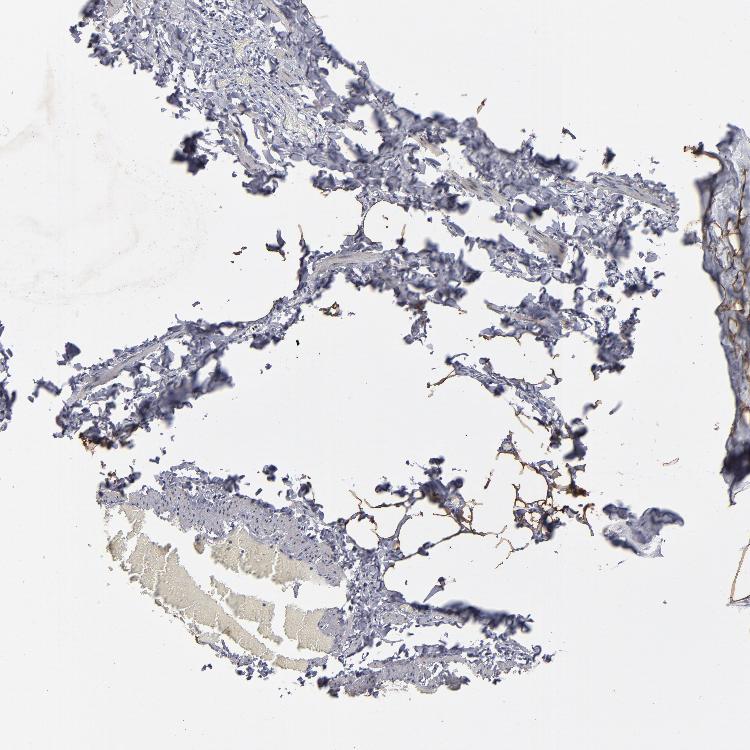

NPAS3